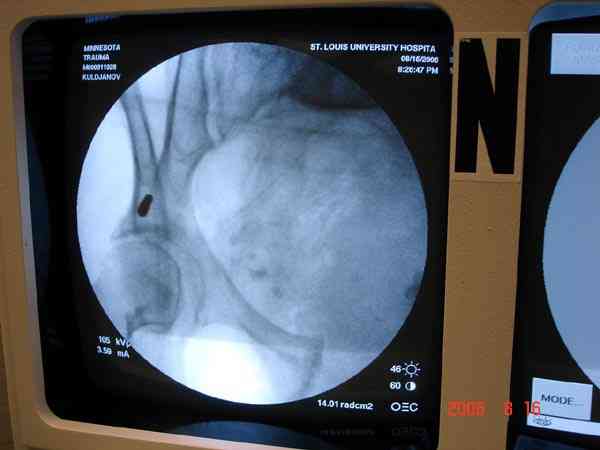

Примерно такой фиксатор наложил вчера ночью, но патология была экстренная травма: больному 53 года, поступил после мотоциклетной травмы, черепно-мозговой, абдоминальной, челюстно лицевой с потерей одного глаза, сосудистой и из скелета перелом крестца слева с диастазом симфиза и множественные переломы ребер.

Здесь соблюдался алгоритм больному с внутритазовым кроветечением после нестабильного перелома таза.

Для стабилизации перелома и кровопотери, сперва была попытка наложения простыни вокруг таза для уменшения объема таза. Для оперативного доступа в области живота и передней части таза простыню заменили на Beam Bag (матрац который после удалении воздуха принимает контуры тела).

Одновременно с хирургами, которые занялись ксплоративной лапаротомией, мы приступили к фиксации временным аппаратом для уменьшения диастаза симфиза. После установки аппарата удалось стабилизировать давление, потом наше место занял сосудистый хирург, который нашел кровоточащую левую артерию epigastrica. Кровоточаший сосуд затромбизировал эндоваскулярно введением 4 coil placement.